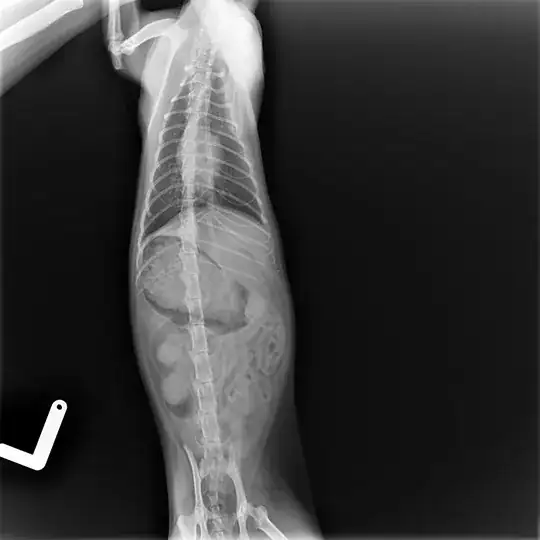

Beside that, we went to a vet to check this cat, blood test, temp., x-ray... so after taking x-ray we saw that her ribs have a strange shape. Local vet says that it seems that this cat suffered possible impact in that area, but he is not sure.

My question is; is it possible that x-ray is mistaken, because of a sudden movement?

Also second x-ray in different cat position shows different shape of ribs.

Can anyone explain, how can I interpret it?